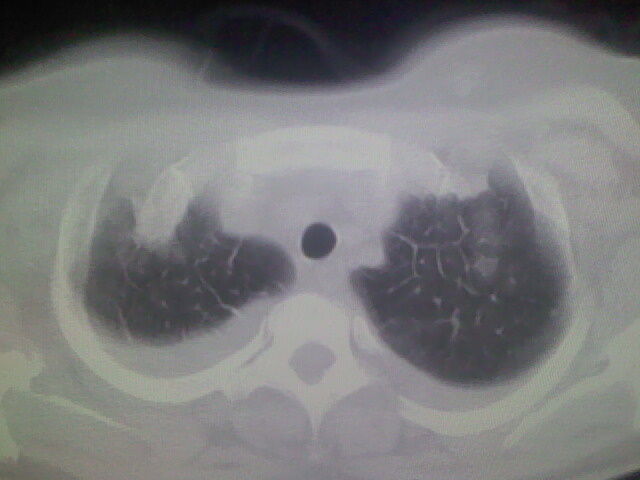

女,24,剖腹产后,突觉胸痛,干咳,不能平卧

胸水 感染 心影增大 肺水肿?

双肺“肺泡性肺水肿” “胸腔积液”!

考虑肺梗塞、肺水肿,双侧胸腔积液